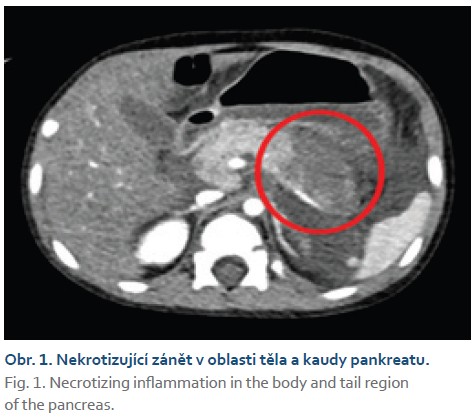

Chlapec (2,5 roku) byl hospitalizován na naší klinice pro akutní lymfoblastickou leukemii. V rámci protokolární léčby byla podána 10. den po jejím zahájení pegylovaná L-asparagináza (PEG-ASP). Pátý den po podání PEG-ASP se u chlapce objevily subfebrilní teploty. Vzhledem k souběžné výrazné leukopenii po předchozí chemoterapii byla zahájena antibiotická léčba. Následující den došlo laboratorně k výrazné elevaci sérové lipázy (27 μkat/l), kterou na našem pracovišti po podání asparaginázy pravidelně monitorujeme. Rozvoj pankreatitidy je totiž známým důsledkem toxicity asparaginázy [5–8]. Chlapec byl klinicky unavený, bledší. Na bolesti břicha si nestěžoval, nezvracel. Bylo doplněno ultrasonografické vyšetření břicha, v němž nebyl pankreas přehledný. Proto jsme doplnili CT vyšetření břicha, které odhalilo nekrotizující zánět pankreatu v oblasti kaudy a části těla s přítomným ascitem (obr. 1). Byla zahájena infuzní terapie a vyloučili jsme perorální příjem. Analgetika chlapec nevyžadoval. Postupně došlo na zavedených opatřeních k normalizaci hladin sérové lipázy, kontrolní USG pankreatu odhalilo suspekci na tvořící se pseudocystu. Zbývající část indukční fáze léčby ALL zvládl chlapec bez dalších významnějších komplikací, na jejím konci dosáhl cytologické remise. V průběhu další protokolární léčby již PEG-ASP podána nebyla.